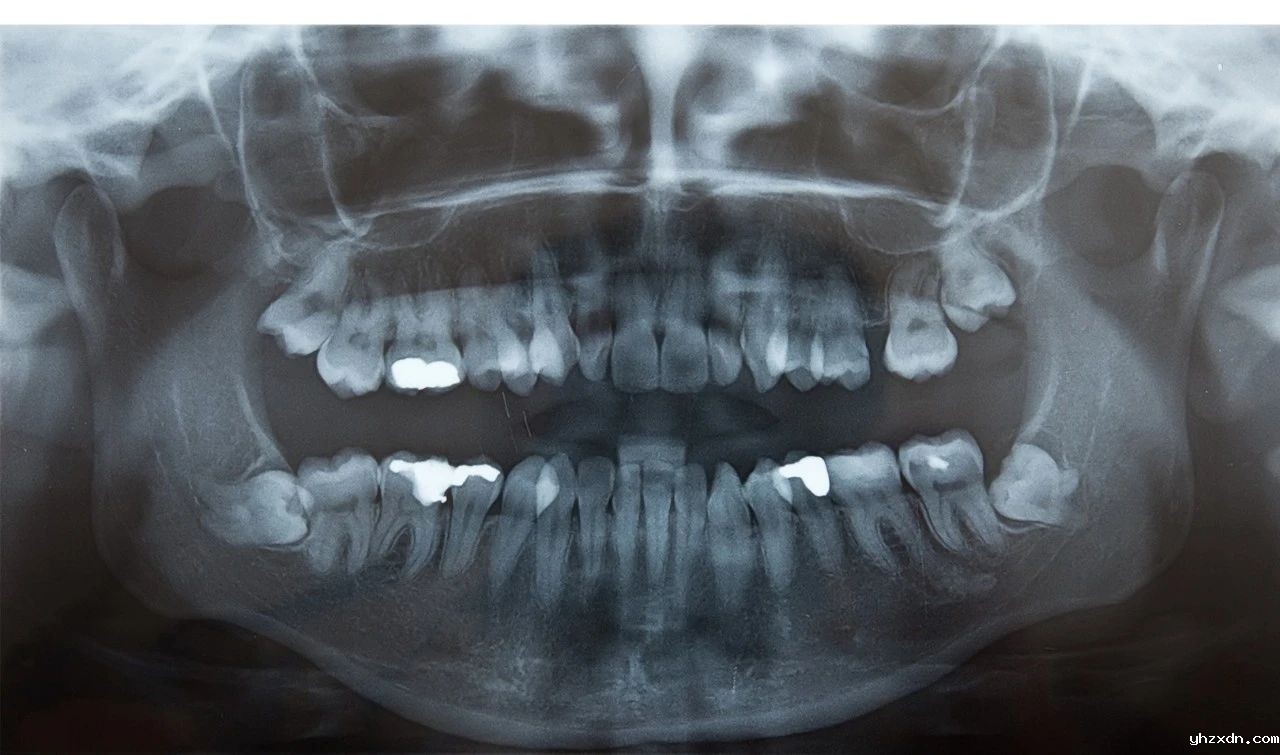

Consultation: A dentist or oral surgeon will examine your teeth and review imaging. Use of panoramic X-rays or CBCT scans is common to evaluate tooth position and proximity to structures like the mandibular nerve or maxillary sinus. Your surgeon will use this data to plan for incision design, bone removal, and extraction technique to minimize trauma and will clearly explain the procedure and post-op care to alleviate patient concerns.